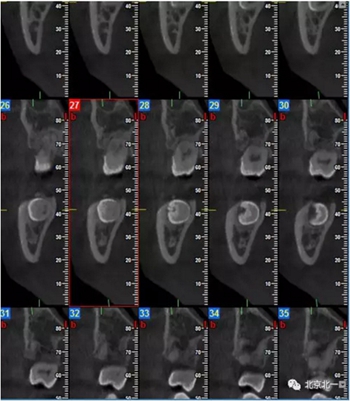

CBCT:骨量高度及寬度可, 48埋伏,低位阻生.37近中骨吸收

診斷:下頜牙列缺損, 48低位埋伏阻生 37 牙周炎

治療計(jì)劃:46種植, 同期拔除48 正畸扶正47.